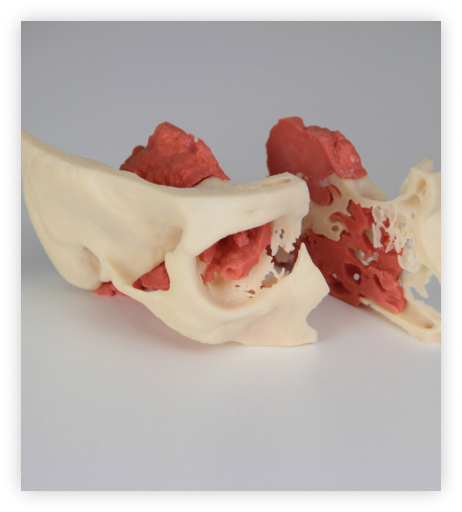

Asthi - Bone-Like 3D Printed Training Models

Our bone-like training models are made from a durable, bone-like material that closely mimics the texture and feel of real bone. These models are perfect for practising surgical techniques and procedures, as they provide a realistic simulation of human bone. Making it easier for medical professionals to study and understand human anatomy. Our models are available in various sizes and can be customised to meet your specific needs.

Asthi- Patient-specific 3D printed bone models

3D-printed bone models made of human bone-like material are accurate and highly detailed, providing a realistic representation of the patient’s bone structure. Our models are ideal for surgical training and planning, allowing medical professionals to practice and perfect their skills before performing surgeries on real patients. as they provide a realistic simulation of human bone. Making it easier for medical professionals to study and understand human anatomy”.

Orthopedics